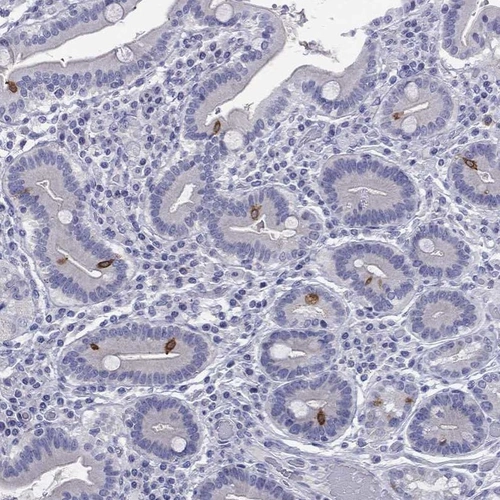

Immunohistochemical staining of human duodenum shows strong cytoplasmic positivity in glandular cells.